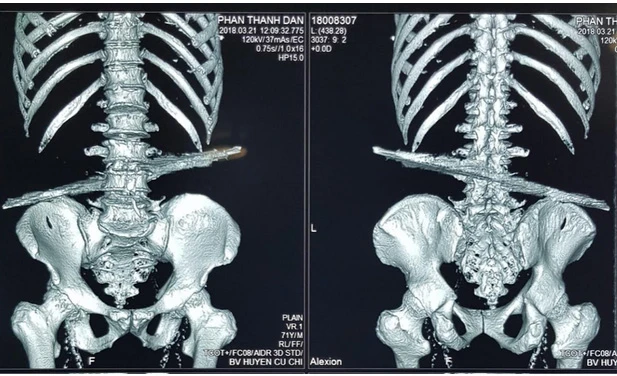

Kết quả chụp X-quang cho thấy nạn nhân bị thanh sắt đâm xuyên phần lưng. Ảnh: VÕ XUÂN

Sau khi chẩn đoán, các BS ghi nhận nạn nhân bị thanh sắt gỉ sét dài khoảng 40 cm đâm ngang vùng thắt lưng. Thanh sắt còn làm vỡ bản sống, gai ngang đốt sống thắt lưng thứ tư của nạn nhân. Trước tình trạng nguy kịch, các BS nhanh chóng đưa nạn nhân vào phòng mổ.